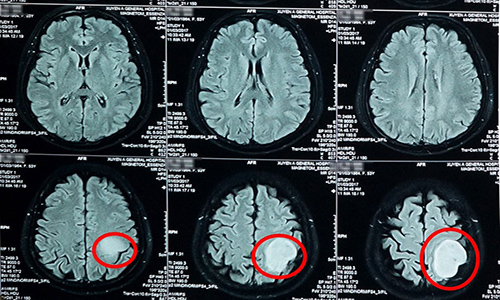

Phát hiện khối u não qua hình ảnh MRI